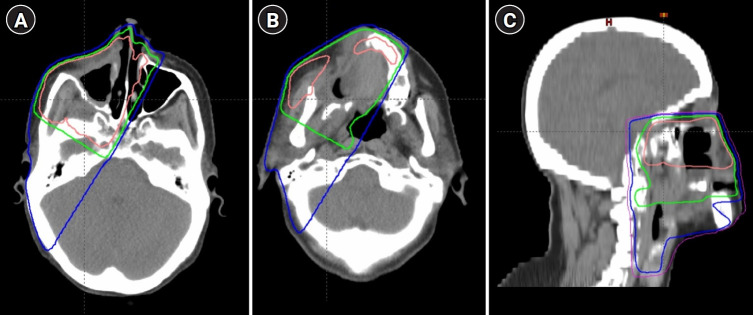

Materials and methods: In this single-institution study, we retrospectively retrieved and analyzed data of patients with sinonasal carcinomas who underwent radiotherapy during 2011-2016 as part of their treatment. The 3-year rate of local, regional, and distant recurrences, and overall survival were evaluated according to the histological type.